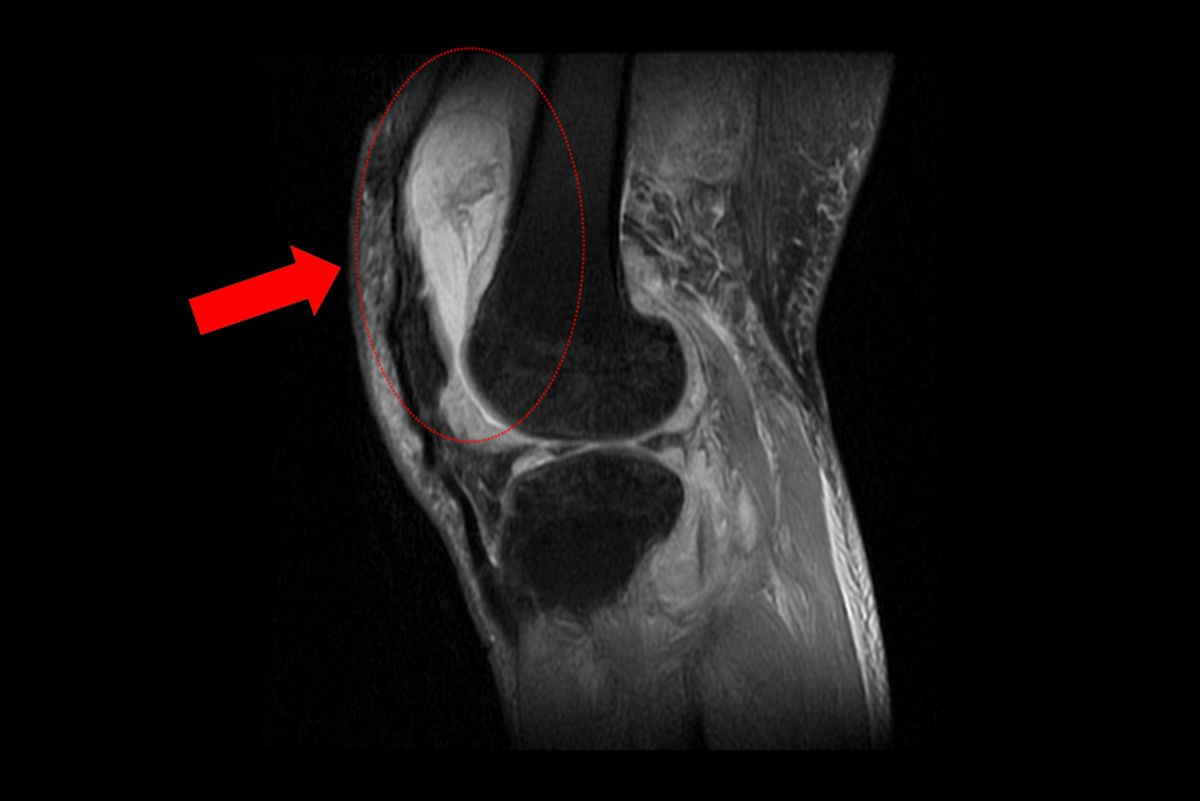

►磁振造影顯示膝蓋內已有大量積液並出現化膿。

賴先生長期左膝腫痛、幾乎無法行走,就診時表示以為只是退化性關節炎,服用止痛藥、抽關節積水、熱敷復健數月卻越來越嚴重,來院時膝蓋已腫脹無法彎曲。關節中心主任周立展抽取膝關節液化驗後發現,白血球數值雖偏高,但並非典型的細菌感染,懷疑有其他原因。周主任安排病人住院,進一步X光與磁振造影檢查,顯示膝蓋內已有大量積液並化膿,屬於嚴重關節感染。